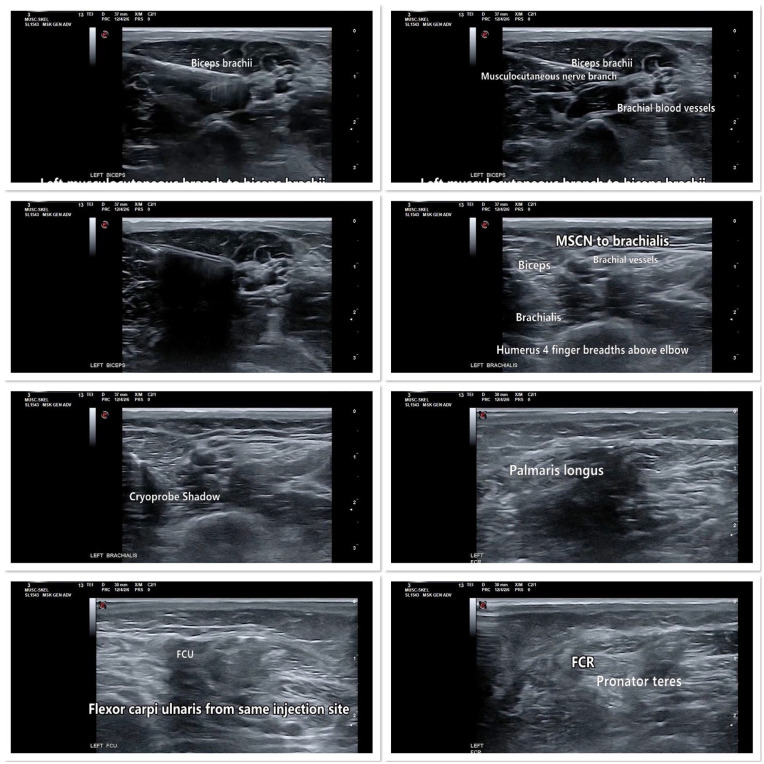

Spasticity affects up to 80% of individuals with cerebral palsy and can lead to pain and difficulties with performing activities of daily living. If left untreated, spasticity can progress to contracture and neuro-orthopedic deformities. Cryoneurolysis is an emerging and mini-invasive ultrasound-guided technique that causes secondary axonotmesis of peripheral nerves through the formation of an ice ball and may result in months to years of improved range of motion and reduced pain in patients with spasticity. However, the safety of cryoneurolysis has not yet been established in patients with an increased bleeding risk secondary to Hemophilia A. We present a case of cryoneurolysis for cerebral palsy-related spasticity in a 14-year-old male with hemophilia A who previously had minimal benefit from botulinum toxin for increased elbow and wrist flexor tone with contracture. Fifteen minutes prior to cryoneurolysis, an IV infusion of 2000 IU of recombinant antihemophilic factor (FVIII) was administered for bleeding prophylaxis. Targets were identified with ultrasound guidance and nerve stimulation and cryoneurolysis was performed without bleeding complications or adverse events. There was an immediate improvement in tone and range of motion that was maintained at 3- and 8-month follow-ups with reported increased left arm function. This case suggests that cryoneurolysis is an effective mini-invasive procedure for spasticity that improves tone and range of motion and is safe for use in patients with Hemophilia A who receive adequate Factor VIII prophylaxis.